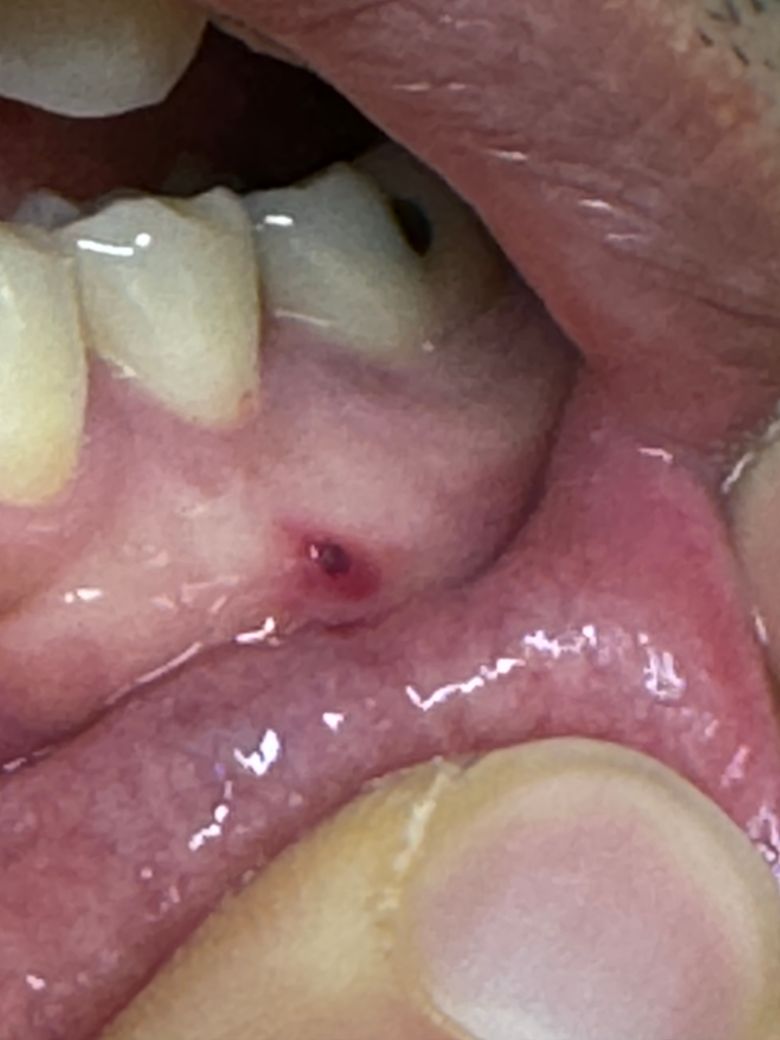

잇몸에 뭐가났는데요 이거 병원에가야되나요?

음식물을 먹다가 찔린적은 없는것같은데

잇몸에 사진처럼 약간 피고임?

그리고 잇몸이 부었더라구요

• 1번 째 사진

사진상으로는 단순 상처로 보입니다. 혹시 크기가 계속 커지거나 잘 낫지 않으면 치과 가보시는 게 좋습니다.

사진으로 보아서는 찔린 흔적으로 보여지지만 시간이 지나도 지금과 같은 상태가 나타난다면 x-ray 등으로 평가를 한 번 받아보는 것이 필요해보입니다. 지금 상태에서는 정확한 판단이 어려우며 통증이나 불편감이 지속되거나 나타난다면 반드시 치과를 방문해보시길 바랍니다.

• 안녕하세요 치과의사 김철진입니다. 잇몸에 상처가 난것같습니다. 아프거나 불편하시면 치과에 가셔서 엑스레이 사진을 한번 찍어보시는게 좋을것같습니다.

• 사진으로만 봤을 경우에는 음식을 먹다가 잇몸에 상처가 난 후 조직 내부에서 출혈이 된 것으로 보입니다 크게 문제가 되진 않을 것으로 생각되나 잇몸에 자극을 주는 너무 딱딱하거나 날카로운 음식을 먹는 빈도를 줄이는 것이 좋습니다

• 주변치아 속 신경 내지는 잇몸에서 비롯된 농양 같습니다 피와 함께 고름이 섞여있고 약간 피가 굳어서 저렇게 보이는 것 같습니다 잇몸치료 내지는 신경치료를 받으시기 바라겠습니다